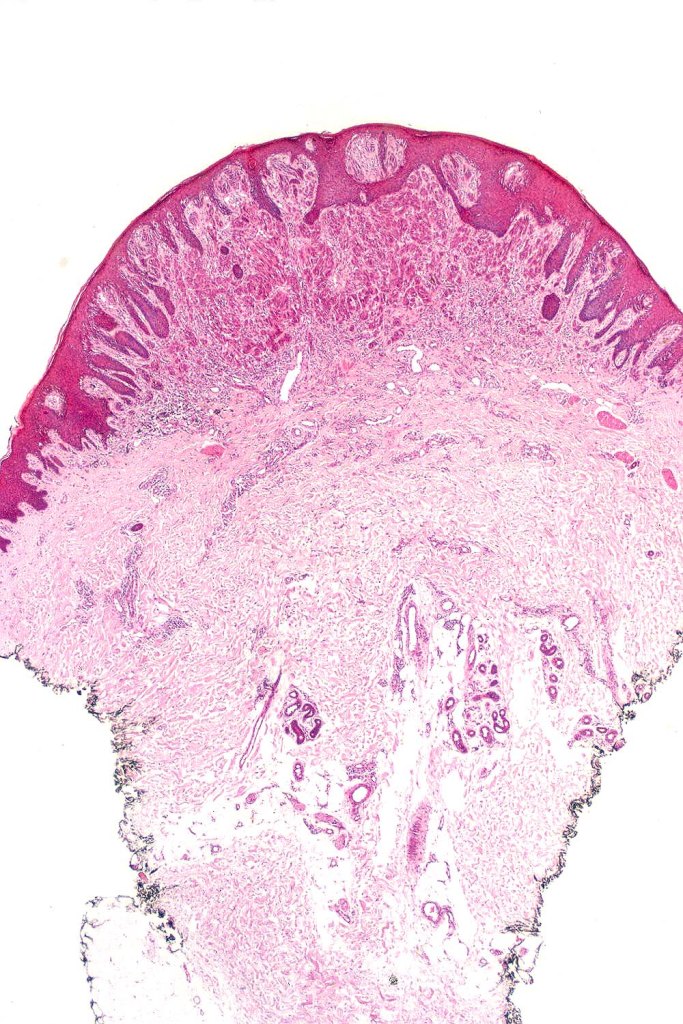

•Sharply circumscribed (begins and ends with a nest), symmetrical dome-shaped lesion. Symmetry is both horizontal and vertical (see image below)

•Wedge-shaped with the base uppermost or sometimes plaque-shaped silhouette

•Hyperkeratosis & acanthosis, sometimes very marked

•Pseudoepitheliomatous hyperplasia

•Superficial vascular ectasia very frequently present